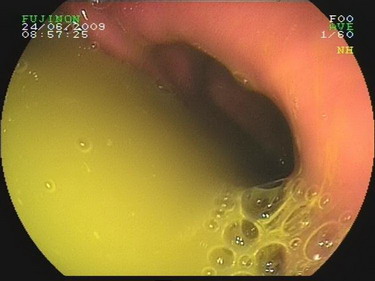

2009.6.24胃镜:

慢性浅表性胃炎,十二指肠淤滞症原因待查,肠系膜上动脉压迫综合症?(胃内可见胆汁样物反流,十二指肠球扩张,降部明显扩张,水平部远端似可见狭窄,持续充气肠腔不能打开。)